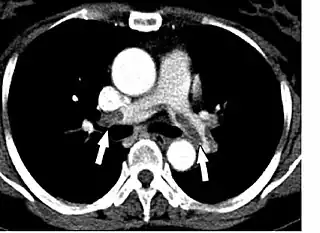

La embolia pulmonar (EP) es un bloqueo de las arterias pulmonares.[8] La mortalidad de EP es aproximadamente 100,000 por año en los Estados Unidos. Es posible que sea más alta recientemente.[9] La embolia es típicamente un coágulo, pero puede ser aire o grasa en casos raros. En la mayoría de casos, el coágulo se origina en las venas de las piernas o la pelvis.[8] Se llama la trombosis venosa profunda (TVP).[10][11] Los factores de riesgo son cualesquiera condiciones que pueden causar la coagulación. Incluye enfermedades genéticas, trastornos autoimunes, el embarazo y el cáncer. Cirugías que requieren inmovilización aumentan el riesgo de EP.[12] Covid-19 también está asociada con la formación de coágulos.[13]

La obstrucción del coágulo aumenta la resistencia en la circulación pulmonar. Se llama resistencia vascular pulmonar. El flujo de sangre a los pulmones disminuye. El ventrículo derecho necesita bombear más fuerte. Si el coágulo es suficientemente grande, la insuficiencia cardíaca derecha resulta. El choque obstructivo y posiblemente la muerte siguen.[8]

Se puede clasificar EP según la gravedad. La embolia pulmonar masiva causa hipotensión y shock. En la clase de embolia pulmonar submasiva, es una que causa disfunción del corazón derecho sin hipotensión.[12]

La embolia pulmonar presenta con dispnea e hipoxia. Un síntoma frecuente es dolor del pecho, peor con la inspiración. El dolor también puede ser similar a la angina debido a la disfunción del corazón derecho.[8] Otros síntomas incluyen síncope y hemoptisis.[22] Si haya una TVP, haría dolor, enrojecimiento, o hinchazón de la pierna.[10] Se puede evaluar la probabilidad de embolia pulmonar a través de varios criterios. La escala de Wells es uno de los criterios más utilizados. Se da puntos según los síntomas y factores de riesgo del paciente.[8][22]

La ecocardiografía también evalúa por las causas de choque obstructivo. Detecta un derrame pericárdico con facilidad.[24][25] Además, en el taponamiento cardíaco, se puede ver el colapso de las cámaras del corazón.[20] En el caso de embolia pulmonar masiva o submasiva, se vería el ventrículo derecho dilatado. Otros signos ecocardiográficos son coágulos en el corazón derecho y el movimiento paradójico del tabique interventricular. Al otro lado, la angiografía por TC es la prueba preferida para diagnosticar la embolia pulmonar.[12]